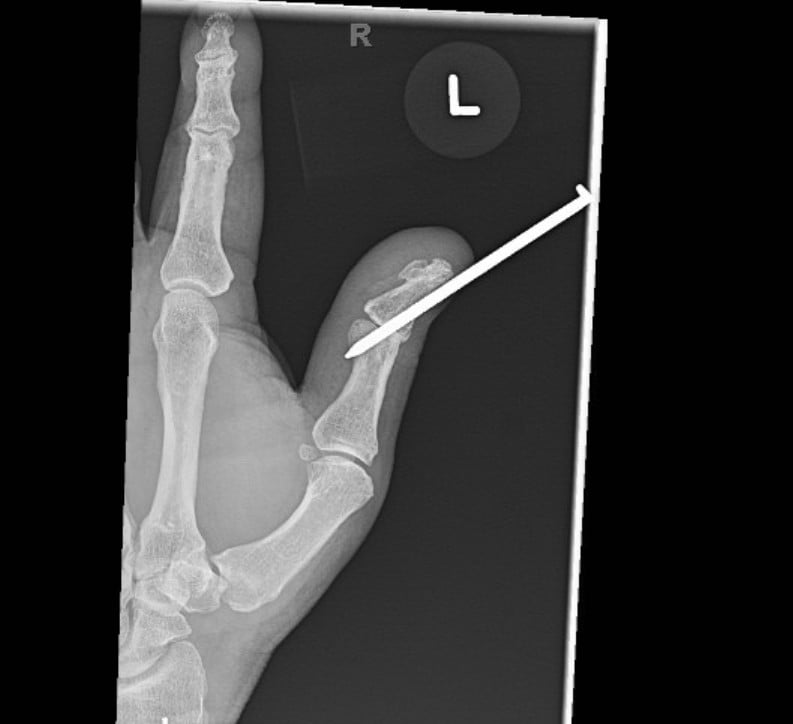

The management of removal of foreign objects from the extremities and phalanges is essential in emergency medicine management; in particular, understanding of the mechanism of injury and details about